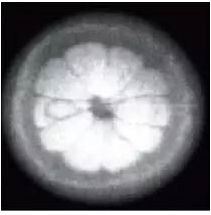

罗伯洛赫尔开启对核磁共振的研究并得到放射

学界众所周知的核磁共振图像诺丁汉的橙子

丁汉的橙子和首次头颅 MR 成像